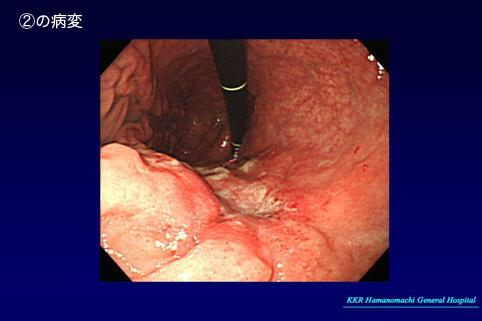

질환(병리주체)의 분류 악성 상피성종양/기타

부위(장기별) 위(부위)/위각

검사방법 내시경

종양의 육안분류 3형(궤양침윤형)/

종양의 최대경(밀리미터) 25~29

종양의 심달도 mp

다발종양(동일 장기) 유(동시성)